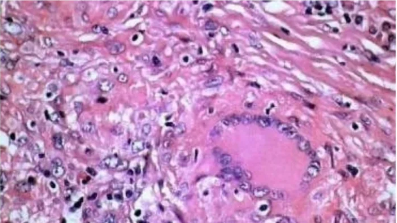

1.Gomori氨银染色法

用途及原理:网状纤维呈黑色,胶原纤维呈红色。鉴别诊断中的应用:①癌和肉瘤的鉴别;②恶性淋巴瘤和组织细胞肉瘤;③血管内皮细胞瘤和外皮细胞瘤;④黏液纤维瘤和黏液肉瘤。